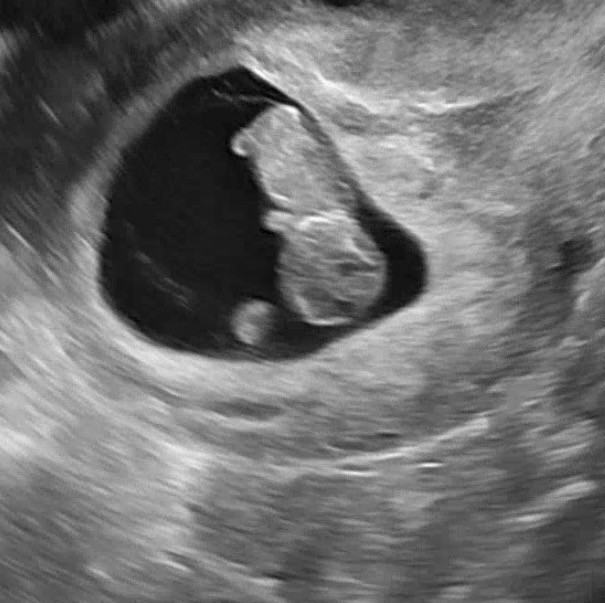

9주 0일차 젤리곰시절 저도 자랑해봐용😖❤️

처음엔 가만히 있다가 촘파 보는줄아는지 꼬물꼬물 움직이는데 너무 귀여워요ㅠㅠ